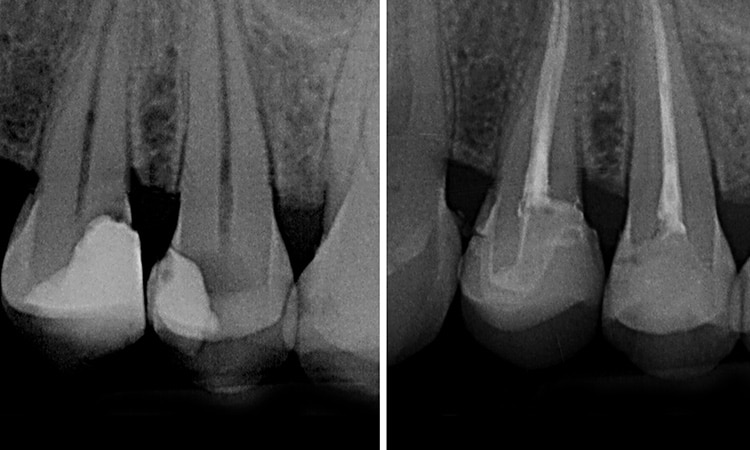

Root Fillings Or

Root Canal Treatment

Deep decay or injury can cause the nerve within the tooth to become painful or to die. The nerve then becomes infected and if left untreated the infection can spread from within the tooth out of the root and into the surrounding bone and gum.

Root canal treatment involves removing all of the infection from within the tooth, filling and sealing it to prevent further infection and to eliminate pain. Once the infection from within the tooth is treated, the infection around the tooth is resolved too.